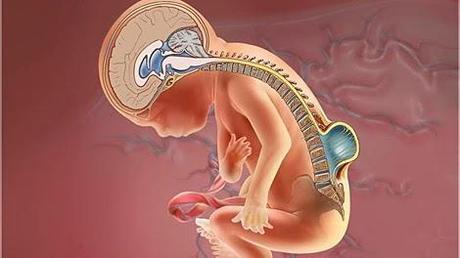

Unos defectos congénitos graves del cerebro y la espina dorsal conocidos como defectos del tubo neural se han reducido en un 35 por ciento en Estados Unidos desde la introducción de la fortificación obligatoria con ácido fólico de los productos de granos enriquecidos en 1998, reportaron el jueves las autoridades federales.Esa reducción significa que, cada año, nacen 1,300 bebés menos con defectos del tubo neural como espina bífida, el defecto del tubo neural más común que, en los casos graves, puede provocar una parálisis parcial o completa de las partes del cuerpo por debajo de la cintura.Pero incluso con la fortificación con ácido fólico, algunas mujeres no ingieren suficiente vitamina B, sobre todo las mujeres hispanas, según los Centros para el Control y la Prevención de Enfermedades (CDC) de EE. UU.La agencia señaló que todas las mujeres en edad fértil, aunque no estén planificando un embarazo, deben consumir 400 microgramos al día de ácido fólico a partir de alimentos fortificados, complementos, o ambas cosas, y consumir alimentos ricos en ácido fólico.

Unos defectos congénitos graves del cerebro y la espina dorsal conocidos como defectos del tubo neural se han reducido en un 35 por ciento en Estados Unidos desde la introducción de la fortificación obligatoria con ácido fólico de los productos de granos enriquecidos en 1998, reportaron el jueves las autoridades federales.Esa reducción significa que, cada año, nacen 1,300 bebés menos con defectos del tubo neural como espina bífida, el defecto del tubo neural más común que, en los casos graves, puede provocar una parálisis parcial o completa de las partes del cuerpo por debajo de la cintura.Pero incluso con la fortificación con ácido fólico, algunas mujeres no ingieren suficiente vitamina B, sobre todo las mujeres hispanas, según los Centros para el Control y la Prevención de Enfermedades (CDC) de EE. UU.La agencia señaló que todas las mujeres en edad fértil, aunque no estén planificando un embarazo, deben consumir 400 microgramos al día de ácido fólico a partir de alimentos fortificados, complementos, o ambas cosas, y consumir alimentos ricos en ácido fólico. "Todas las mujeres capaces de tener un bebé deben tomar un multivitamínico que contenga ácido fólico todos los días", señaló la Dra. Siobhan Dolan, coautora de un libro de March of Dimes, Healthy Mom, Healthy Baby: The Ultimate Pregnancy Guide, en un comunicado de prensa de la organización."También es bueno consumir alimentos que contengan folato, la forma natural del ácido fólico, como las lentejas, las verduras de hojas verdes, los frijoles negros y el jugo de naranja, además de alimentos fortificados con ácido fólico, como el pan y la pasta, y los cereales enriquecidos", añadió.Otro estudio de los CDC publicado el jueves halló que muchas mujeres estadounidenses que han tenido un embarazo afectado por un defecto del tubo neural y que vuelven a quedar embarazadas no siguen las recomendaciones sobre la complementación con ácido fólico. Los proveedores de atención de la salud deben hacer más por animar a esas mujeres a aumentar su ingesta de ácido fólico, señalaron los autores del estudio.Entre las mujeres con un defecto del tubo neural en un embarazo anterior, apenas el 35 por ciento de las que tuvieron un defecto del tubo neural en un segundo embarazo tomaron ácido fólico, frente al 80 por ciento de las que tuvieron un embarazo libre de defectos congénitos, halló el estudio.Las mujeres que han experimentado un defecto del tubo neural están en mayor riesgo de otro, anotaron los investigadores. Se sabe que los complementos de ácido fólico de dosis alta (4 miligramos al día tomados al menos cuatro semanas antes de quedar embarazada y en las primeras 12 semanas del embarazo) reducen el riesgo de defectos del tubo neural, señalaron los CDC.Las mujeres hispanas tienen alrededor de un 20 por ciento más de probabilidades de tener un hijo con un defecto del tubo neural que las mujeres blancas no hispanas. Un motivo, según March of Dimes, es que la harina de trigo se fortifica con ácido fólico, pero la harina de masa de maíz, que es popular entre los hispanos, no se fortifica.March of Dimes apunta que le solicitó a la Administración de Alimentos y Medicamentos (FDA) de EE. UU. que fortifique la harina de masa de maíz con ácido fólico con el objetivo de reducir la tasa de defectos del tubo neural entre las mujeres hispanas.Ambos estudios aparecen en la edición del 16 de enero de la revista Morbidity and Mortality Weekly Report, publicada por los CDC.